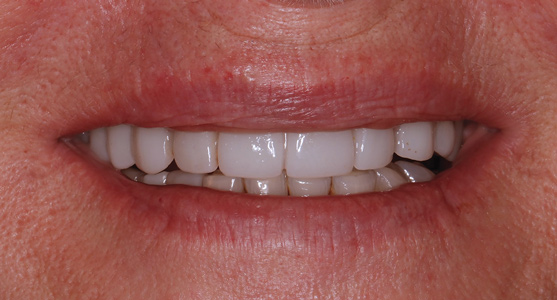

The rigidly fixated provisional was left undisturbed for a minimum of 5 months to allow for osseointegration of the implants. The patient was advised to maintain a soft diet during that time. To prevent fracture of the provisional, cantilevers should be eliminated or minimized and any metal inserts should have at least 4 mm of thickness around them. If any fractures or chips have occurred on the provisional they can be repaired intraorally or extraorally with standard light-cured bisphenol A-glycidyl methacrylate (bis-GMA) or bisacryl composite resins. Figure 14 and Figure 15 illustrate the in-house 3D-printed provisional at 5 months with excellent bone levels on the implants.

Fig 14. Patient’s smile 5 months post-surgery.

Figure 14